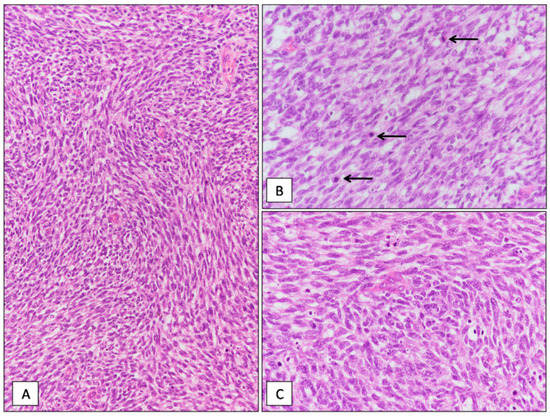

Desmoplastic Small Round Cell Tumor with “Pure” Spindle Cell Morphology and Novel EWS-WT1 Fusion Transcript: Expanding the Morphological and Molecular Spectrum of This Rare Entity

3.1. Histological and Molecular Findings